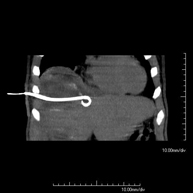

Consisteix en col·locar un catèter de drenatge sobre una col·lecció líquida localitzada a la cavitat abdominal, amb la intenció de buidar el màxim possible aquesta col·lecció. El pacient ha de mantenir el drenatge alguns dies, normalment fins que no sigui productiu. Sovint es realitza sota sedació, amb l'ajuda de l'equip d'anestèsia. Tot el procediment es realitza controlat per imatges obtingudes per Tomografia Computaritzada (TC) en diversos moments de la prova mitjançant l'ús de Fluoroscòpia –TC. Després de la prova, el pacient resta hospitalitzat. És necessari que porti les proves de coagulació abans de la prova.

Consisteix en col·locar un catèter de drenatge sobre una col·lecció líquida localitzada en la cavitat abdominal, amb la intenció de buidar el màxim possible d'aquesta col·lecció. El pacient haurà de mantenir el drenatge uns quants dies, normalment fins que no sigui productiu. Sovint es realitza sota sedació, amb l'ajuda de l'equip d'anestèsia. Tot el procediment es realitza controlat per imatges obtingudes per Tomografia Computaritzada (TC) en diversos moments de la prova mitjançant l'ús de Fluoroscòpia-TC. Després de la prova, el pacient resta hospitalitzat. És necessari que porti proves de coagulació abans de la punció. - Biòpsia òssia guiada per TC